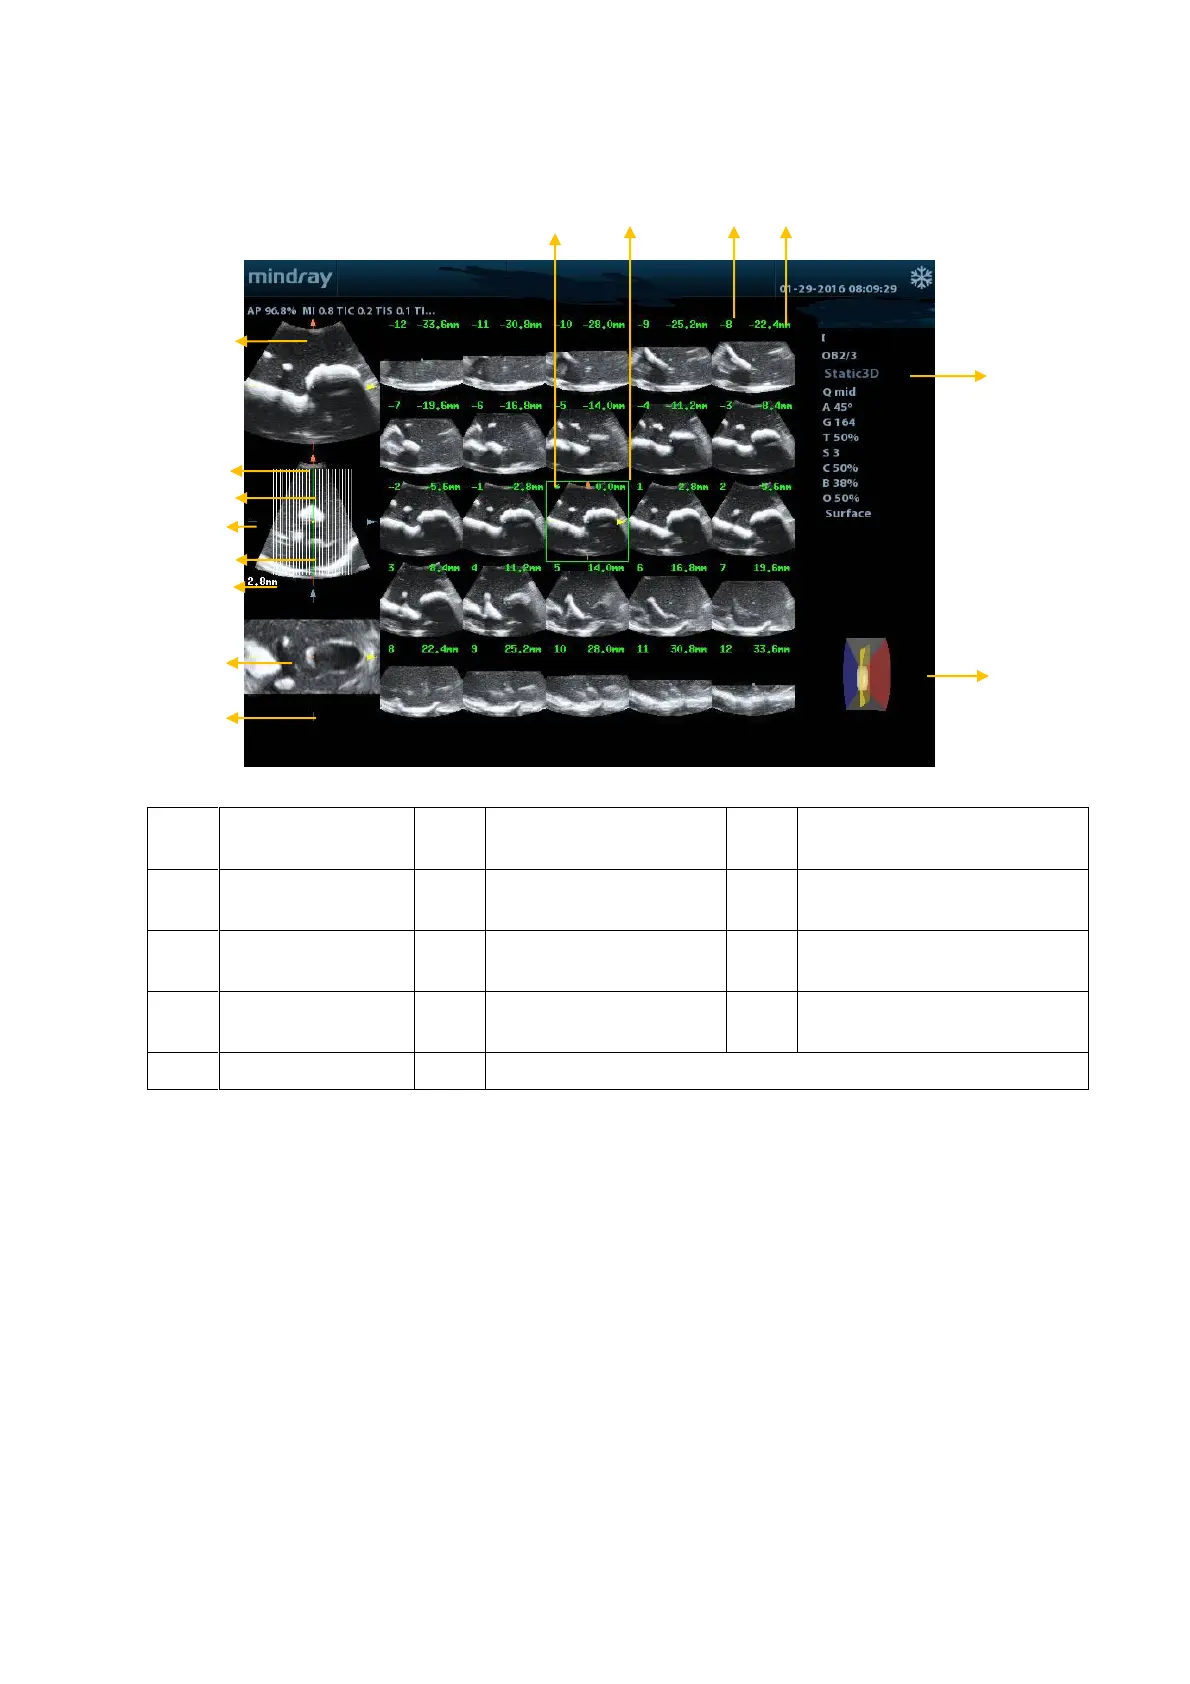

5.12.7.2 iPage Basic Functions and Operations

<1>

A plane

<2>

B plane (the current

reference image)

<3>

C plane

<4>

Y-axis

<5>

X-axis

<6>

Central section line (Current

active section line)

<7>

Section line

<8>

Space between two

planes

<9>

Image parameter

<10>

Wire cage

<11>

Section plane order

number

<12>

Section plane position (to the

central plane)

<13>

Central plane mark

<14>

Green box on the active image

The system supports several types of display layout: 2*2, 3*3, 4*4 and 5*5. Click the

corresponding icon on the screen to select, and the selection [Slice Number] changes

accordingly.

Reference image

Click [A Plane], [B Plane] or [C Plane] to select the reference image.

Slice and slice line

Central slice: the central plane which corresponds to the central slice line is the

central slice, marked with a green “*” in the top-left corner of the image.

View vertical or horizontal slices.

Active slice: the central plane which corresponds to the green slice line is the active

slice, marked with a green box. The default active slice is the central slice.

Slice order number: indicates the order of the slices. The position of the central slice

is “0”, the slices before the central slice are marked with negative integral numbers,

and the slices after the central slice are marked with positive integral numbers.